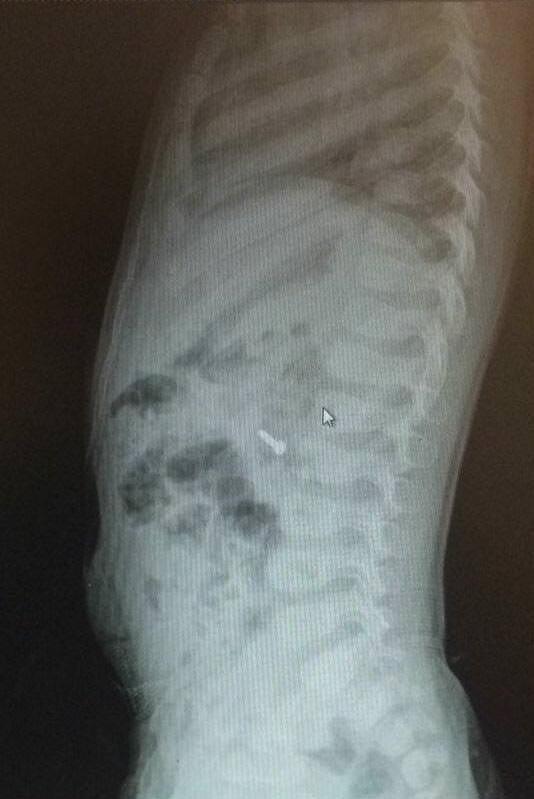

İzmir'deki Tepecik Eğitim ve Araştırma Hastanesi Çocuk Gastroenteroloji Bölümü'nün, yabancı cisim yutan çocukların nefes ve borusu ile midelerinden çıkarttığı, anahtarlık, madeni para, saat pili, ataç, çengelli iğne ve çivi gibi objeler görenleri şaşkına çevirdi.

"Çocukların nefes ve borusu ile midelerinden çıkartılan, anahtarlık, madeni para, saat pili, ataç, çengelli iğne ve çivi gibi objeler görenleri şaşkına çevirdi. "